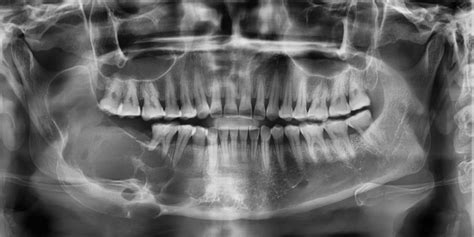

El principal método para detectar un quiste maxilar es a través de una radiografía, en la que se puede observar una mancha de color oscuro en el hueso. Generalmente es necesario realizar una radiografía para diagnosticar esta patología que se manifiesta a través de una zona oscura en el hueso. En la ortopantomografía (radiografía en 2D de toda la boca) el quiste maxilar se observa como una zona oscura y redondeada en forma de bolsa.